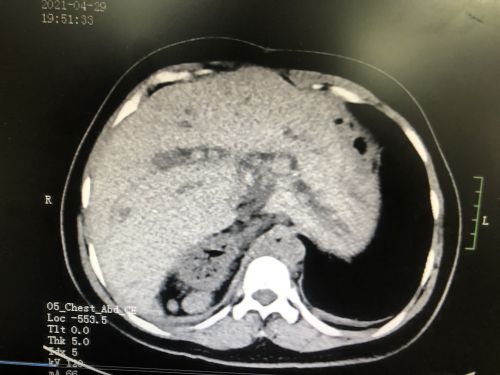

术前ct显示肝胆管多发结石。

入院后的CT检查发现,张女士不仅有“肝胆管结石并胆管炎”,而且脾脏分裂成4个;不仅如此,4个脾脏和胃、十二指肠都长反了位置——本应在腹腔左侧的脾脏和胃跑到右边,而原本应该在右侧的十二指肠则跑到了左边。